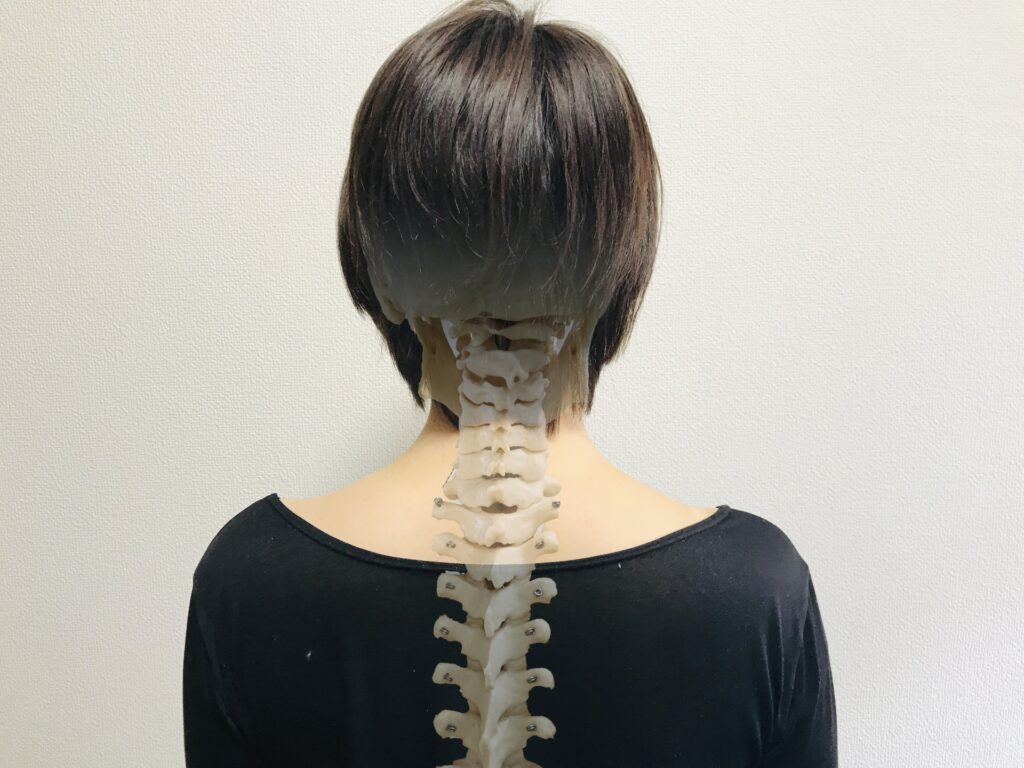

ぎっくり腰は第一頚椎が原因かも!?

ぎっくり腰と聞くと、腰そのものが原因であると考えがちですが、実は第一頚椎(首の一番上の骨)がぎっくり腰の原因となっている可能性もあります。頚椎と腰の関係はあまり知られていないかもしれませんが、全身の骨格は互いに連動しており、首の不調が腰に影響を与えるケースもあるのです。

まず、第一頚椎の役割について簡単に説明します。第一頚椎は頭を支え、首をスムーズに動かす役割を持っています。この部分は非常に繊細で、頭の重さを直接支える重要な骨でもあります。この第一頚椎にズレや歪みが生じると、首周りの筋肉が緊張し、その影響が全身に波及します。特に、背骨全体に影響を与えるため、腰にも負担がかかりやすくなるのです。結果として、腰の筋肉に過剰な負担がかかり、ぎっくり腰を引き起こす原因となることがあります。

また、姿勢の悪さや身体のバランスの崩れも、第一頚椎とぎっくり腰の関係に影響を与えます。例えば、デスクワークで長時間同じ姿勢を続ける、スマートフォンの長時間の使用で首が前に傾く「ストレートネック」の状態になると、首や肩、腰にかかる負担が増します。このような状態が続くと、全身の筋肉が緊張しやすくなり、結果として腰に強い痛みが出やすくなります。つまり、腰に直接問題がないように見えても、首の状態がぎっくり腰の引き金となることがあるのです。

こうした第一頚椎とぎっくり腰の関係を考慮することで、より根本的な対策が可能になります。首と腰の連動性を理解し、腰だけでなく首のケアや姿勢の改善を行うことで、ぎっくり腰の再発防止や痛みの軽減に役立つでしょう。

したがって、ぎっくり腰がなかなか治らない、何度も繰り返してしまうという方は、腰だけでなく第一頚椎の状態をチェックすることをおすすめします。体全体のバランスを整えることで、根本的な痛みの原因を解消し、ぎっくり腰から解放される可能性が高まります。

当院緑ヶ丘カイロプラクティックセンターでは、ぎっくり腰の症状に対して、上部頚椎調整法を中心としたアプローチを行っています。上部頚椎調整法は、首の一番上にある第一頚椎を調整する施術で、全身の骨格バランスを整え、ぎっくり腰の痛みを根本から改善することを目指しています。この施術は、アトラスオーソゴナルカイロプラクティックという手法をベースにしており、痛みの原因を第一頚椎に着目して解消するものです。

上部頚椎は、首と頭をつなぐ重要な骨であり、ここがずれていたり歪んでいたりすると、全身の筋肉のバランスが崩れ、腰への負担が増してしまうことがあります。当院では、この上部頚椎に焦点を当てて調整することで、首から背中、腰に至るまでの緊張を緩和し、全身のバランスを整えるよう施術を行います。この調整により、ぎっくり腰の原因となる筋肉や骨格のアンバランスを解消し、痛みの軽減と早期の回復をサポートしています。